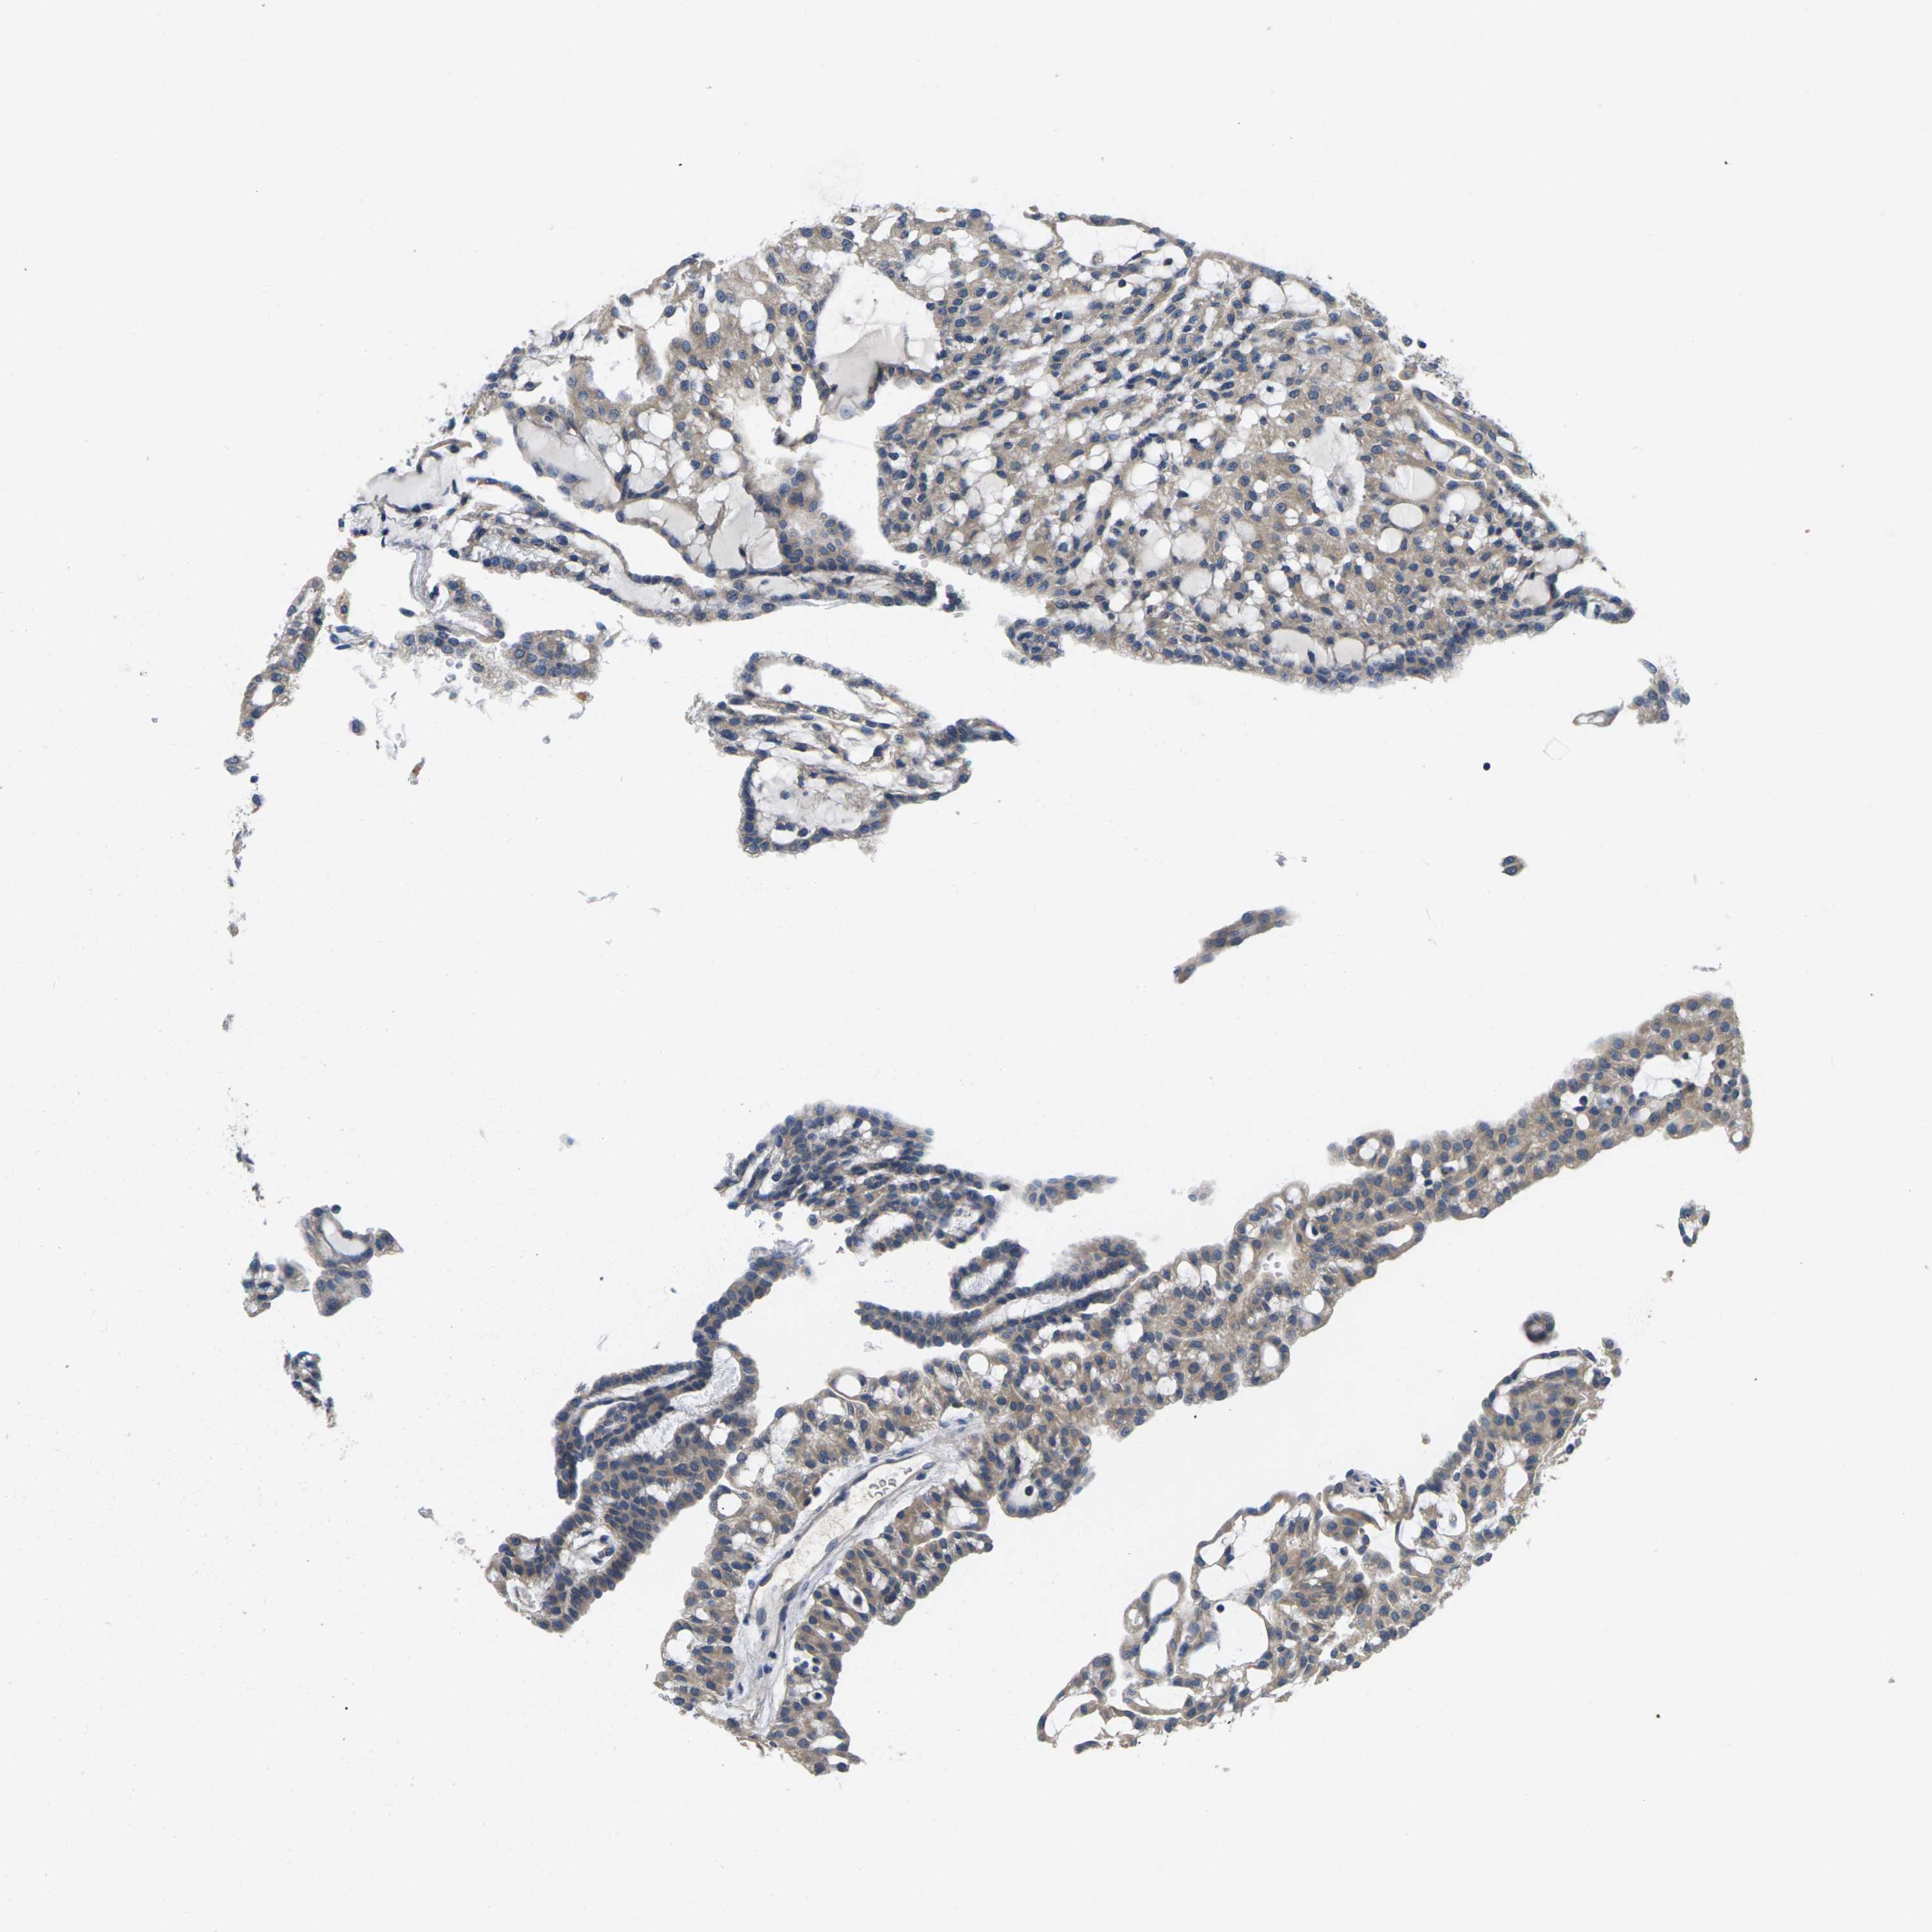

KIDNEY RENAL CLEAR CELL CARCINOMA (VALIDATION) - Interactive survival scatter ploti

The Survival Scatter plot shows the clinical status (i.e. dead or alive) for all individuals in the patient cohort, based on the same data that underlies the corresponding Kaplan-Meier plots. Patients that are alive at last time for follow-up are shown in blue and patients who have died during the study are shown in red.

The x-axis shows the expression levels (FPKM) of the investigated gene in the tumor tissue at the time of diagnosis. The y-axis shows the follow-up time after diagnosis (years). Both axes are complimented with kernel density curves demonstrating the data density over the axes. The top density plot shows the expression levels (FPKM) distribution among dead (red) and alive patients (blue). The right density plot shows the data density of the survived years of dead patients with high and low expression levels respectively, stratified using the cutoff indicated by the vertical dashed line through the Survival Scatter plot. This cutoff is automatically defined based on the FPKM cutoff that minimizes the p-score. The cutoff can be changed by dragging the vertical line or by entering a cutoff value in the square labeled "Current cut-off".

Under the Survival Scatter plot the p-score landscape (black curve; left axis) is shown together with dead median separation (red curve; right axis). Dead median separation is the difference in median mRNA expression between patients who have died with high and low expression, respectively. It is calculated as follows: median FPKM expression of dead patients with high expression - median FPKM expression of dead patients with low expression. This is intended to aid the user in visually exploring custom cutoffs and the associated p-scores and dead median separation.

Individual patient data is displayed and can be filtered by clicking on one or more of the category buttons on the top of the page. Categories describing expression level and patient information include: high, low, alive, dead, female, male and tumor stages. The scale of the x-axis can be toggled between linear and log-scale by clicking on the "x log" button. Mouse-over function shows TCGA ID, patient information and mRNA expression (FPKM) for each patient.

& Survival analysisi

Kaplan-Meier plots summarize results from analysis of correlation between mRNA expression level and patient survival. Patients were divided based on level of expression into one of the two groups "low" (under cut off) or "high" (over cut off). X-axis shows time for survival (years) and y-axis shows the probability of survival, where 1.0 corresponds to 100 percent.

ERGIC3 is potential prognostic, high expression is unfavorable in Kidney Renal Clear Cell Carcinoma (validation)

Best expression cut offi

Based on the FPKM value of each gene, patients were classified into two groups and association between prognosis (survival) and gene expression (FPKM) was examined. The best expression cut-off refers the FPKM value that yields maximal difference with regard to survival between the two groups at the lowest log-rank P-value. Best expression cut-off was selected based on survival analysis .

When clicking on this number, the vertical dashed line indicating cut-off, the interactive survival plot, and the Kaplan-Meier curve will be adjusted to show results based on the best expression cut-off.

: 226.37

TCGA RNA samplesi

RNA-seq data is reported as average FPKM (number Fragments Per Kilobase of exon per Million reads), generated by the The Cancer Genome Atlas (TCGA) .

Normal distribution across the dataset is visualized with box plots, shown as median and 25th and 75th percentiles. Points are displayed as outliers if they are above or below 1.5 times the interquartile range. FPKM values of the individual samples are presented next to the box plot.

Average pTPM 208.4

Number of samples 100